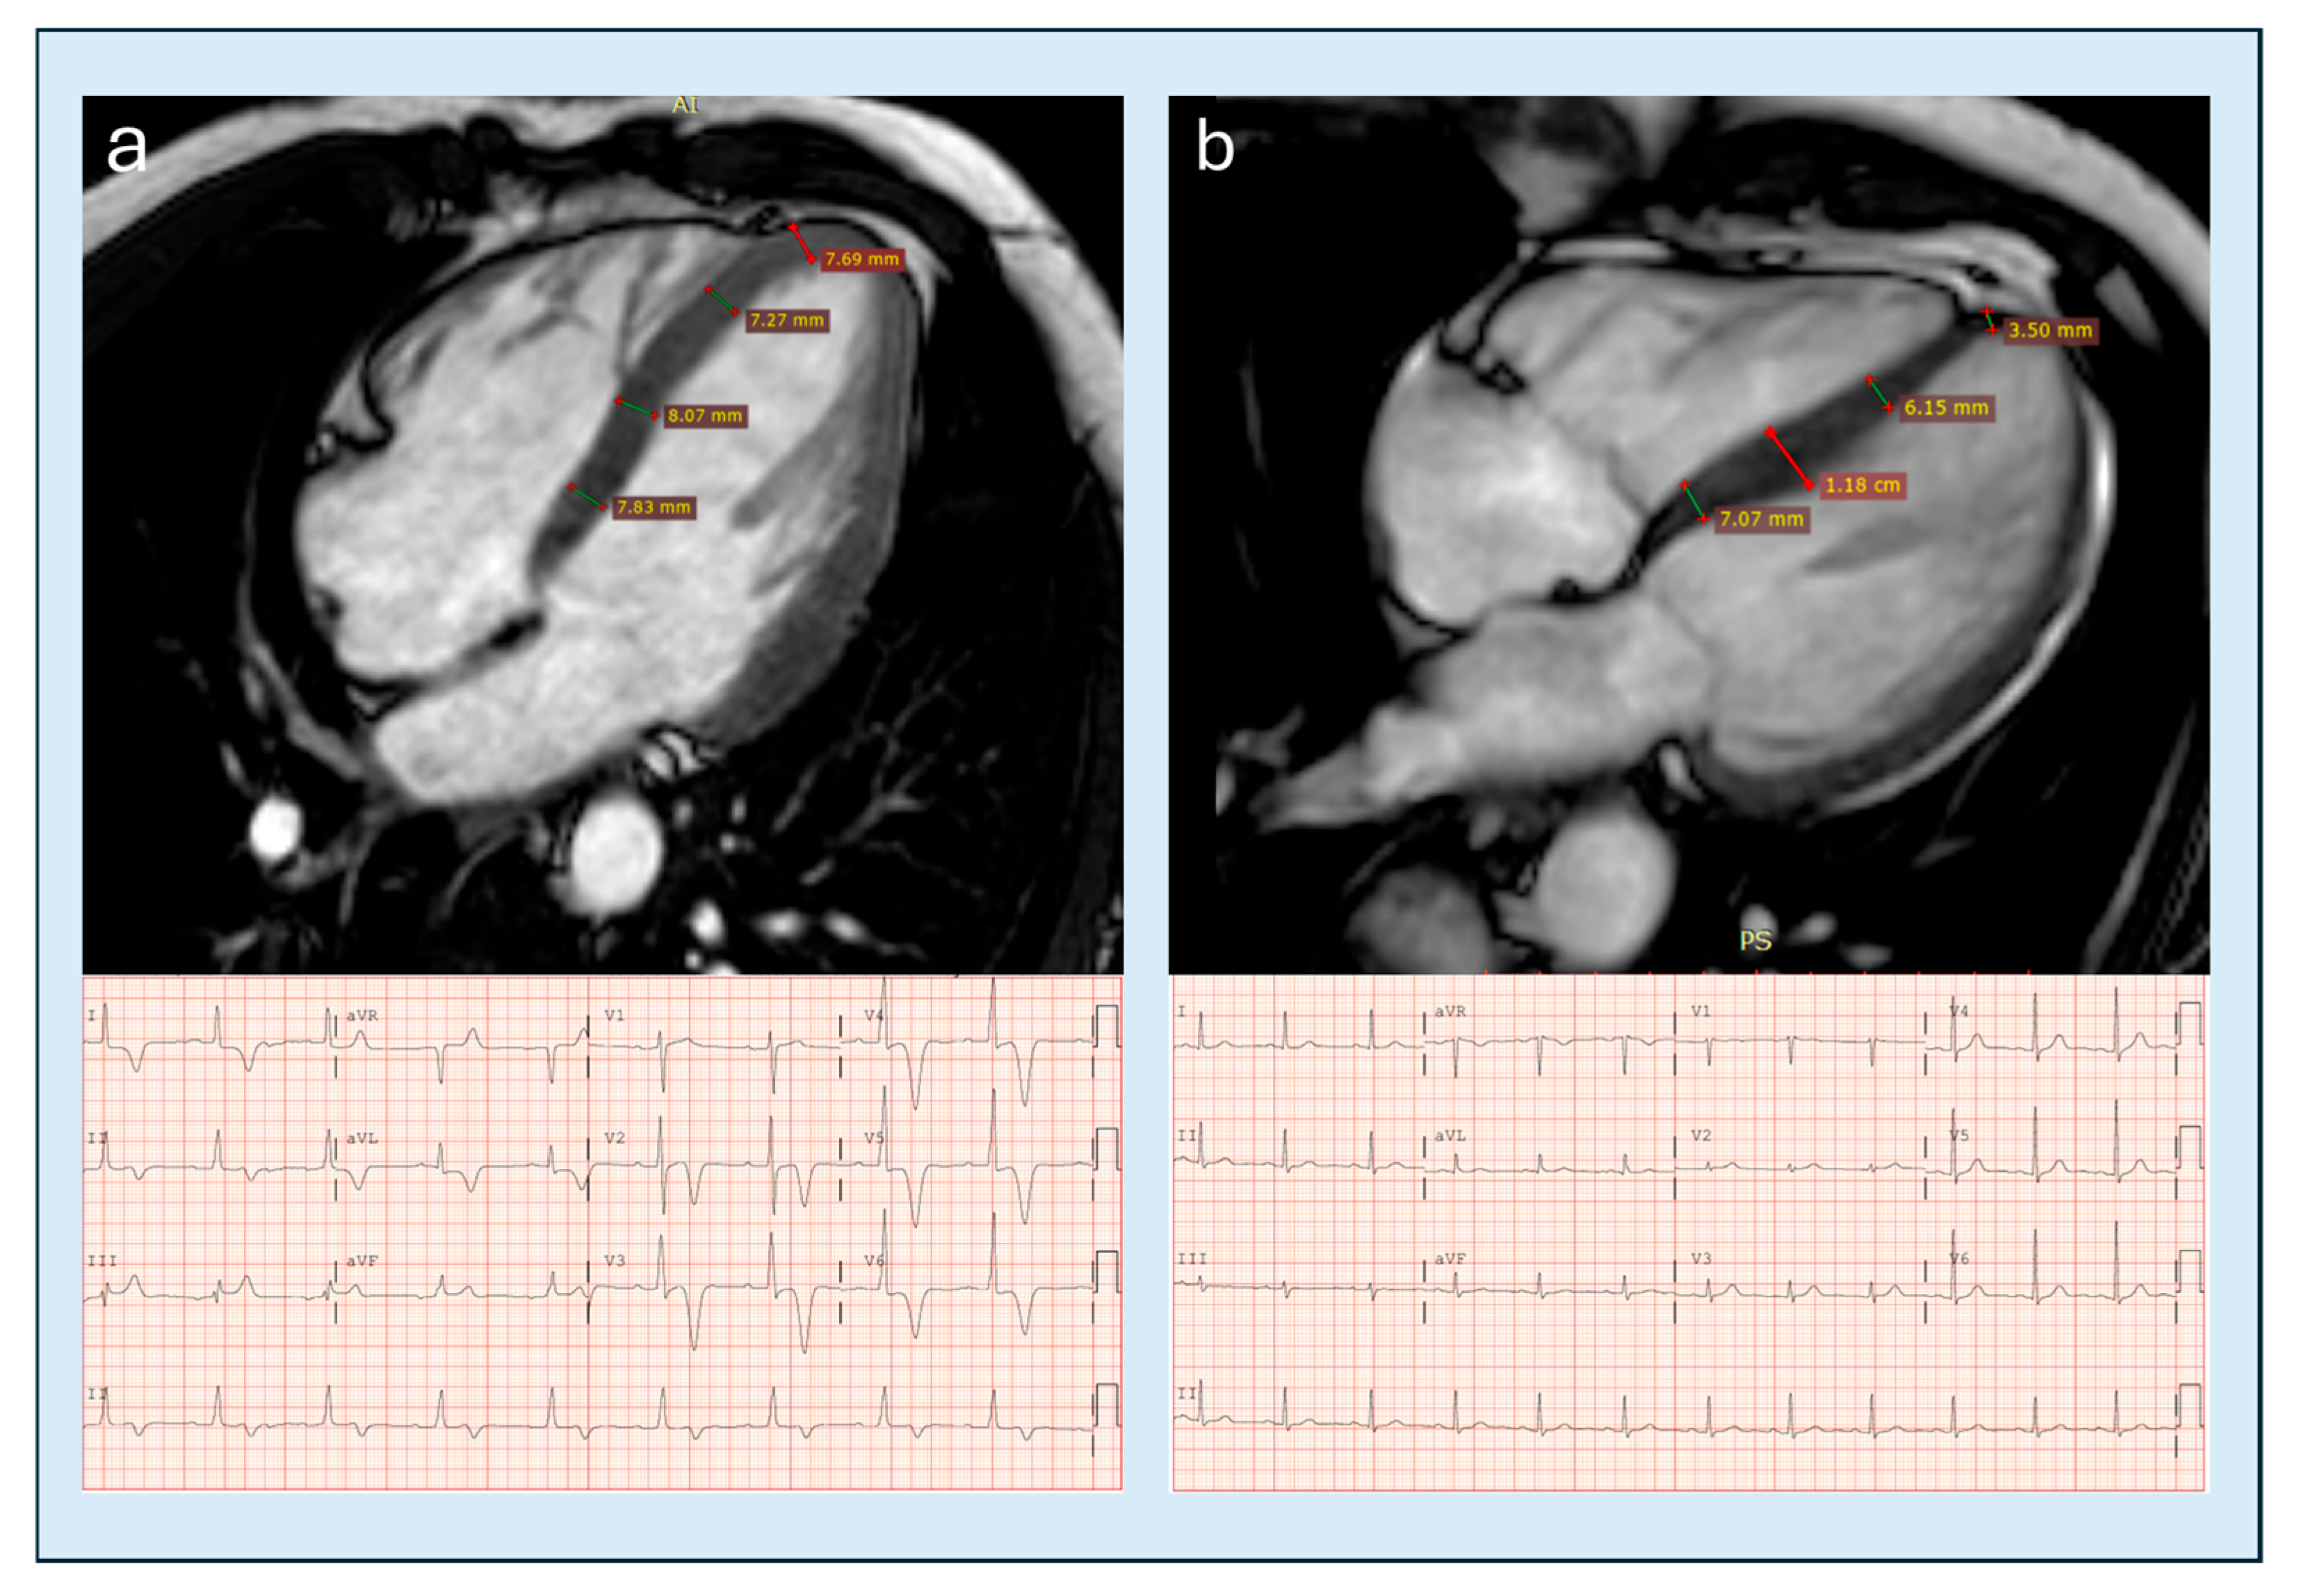

| Indexed apical maximum wall thickness | CMRi | ≥5.2–5.6 mm/m2 | >4000 controls +104 ApHCM pts | AUC 0.94; Sens 99/78%; FP 3% | High | ++ | Hughes 2024 [25] |

| Loss of basal–apical tapering | CMRi | Apical ≥ basal | 22 relative ApHCM vs. controls | Supportive; no AUC | Moderate | +++ | Flett 2015 [74] |

| Apical–basal thickness ratio | CMRi | >1 (prev ≥1.3) | Mixed CMR cohorts | Not available | Moderate | +++ | Flett 2015 [74] |

| Apical angle | CMRi | ≤75–76° | 71 pts | AUC 0.77 | Low–mod | ++ | Li 2021 [64] |

| Apical thickness progression | CMRi | Mean ≥7.6 mm; Max ≥9.5 mm | 71 pts | AUC 0.87–0.898 | Moderate | ++ | Li 2021 [64] |